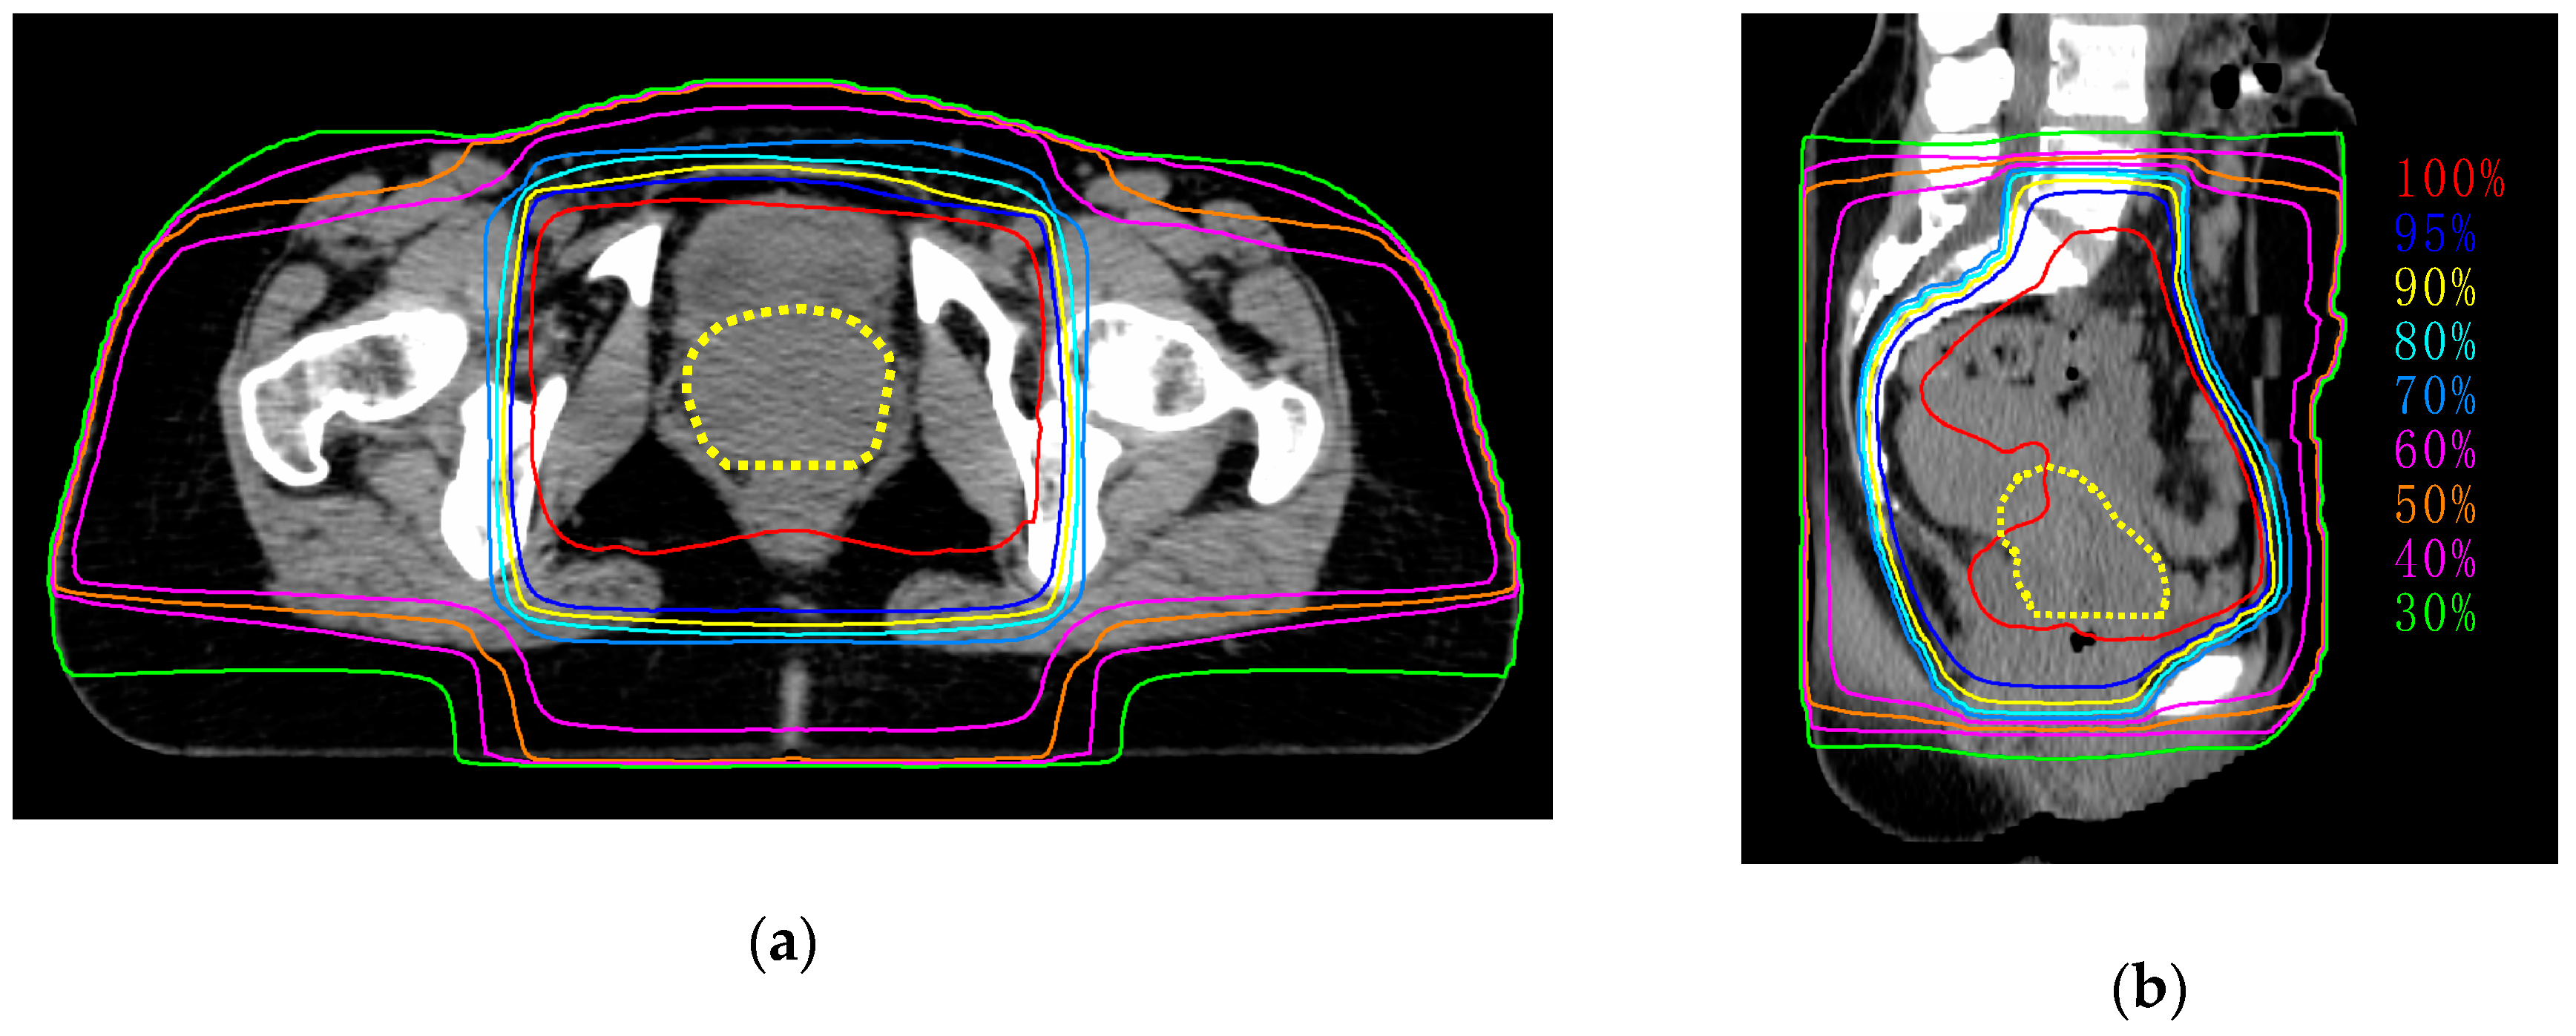

Seven patients were enrolled in this study (Table 1). The median age was 57 (42–82) years. Four patients received concurrent chemoradiotherapy (CCRT) with weekly cisplatin (40 mg/m2), and the remaining three patients received RT alone because of older age (i.e., ≥ 75 years). The median total dose of external beam radiotherapy (EBRT) was 55.6 (50.0–58.0) Gy. We confirmed that more than 95% of the planned doses were appropriately delivered to tumors (Figure 2).

Figure 2.

Representative images of dose distribution of external beam radiotherapy. Dashed line indicates tumor (yellow). (a) Axial plane; (b) sagittal plane.